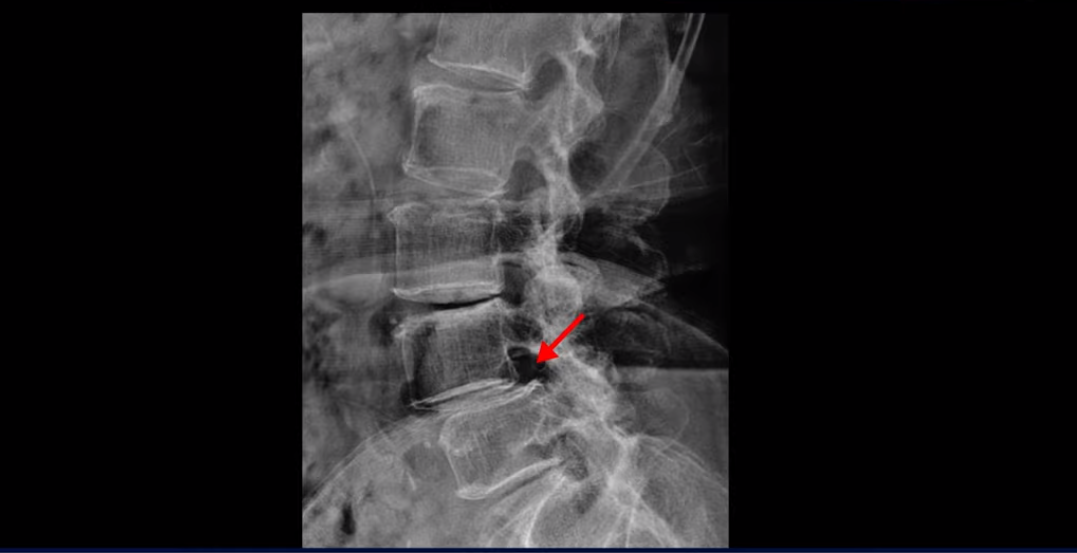

4번 5번에는 뼈가 밀려 나간 전방전위증도 있습니다.

X-ray로 보면 뼈가 밀려 나간 게 더 잘 보입니다.